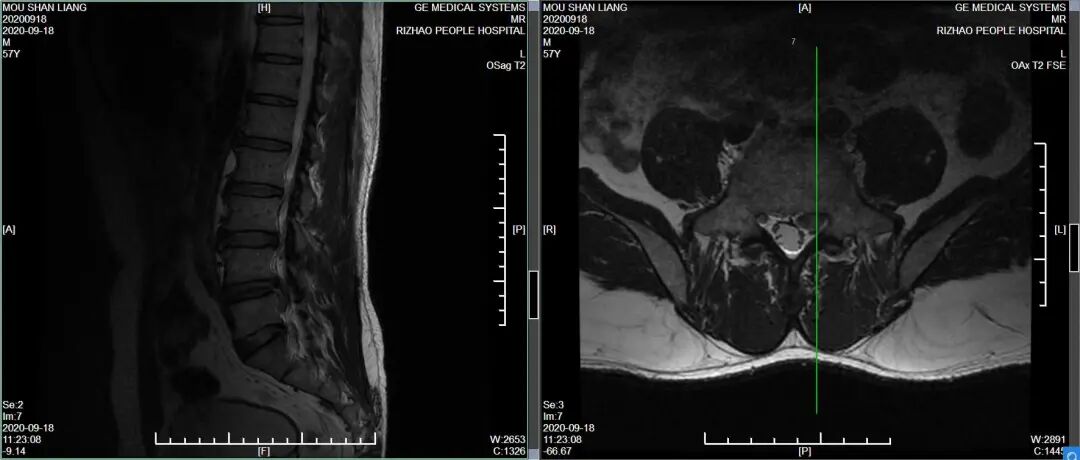

影像学检查:腰椎MRI:

1、L4-5、L5-S1椎间盘突出

2、L2-3、L3-4椎间盘膨出

3、L5椎体后等信号,椎间盘组织脱垂可能

4、腰椎骨质增生

5、腰部皮下软组织局部轻度水肿

图2:术前影像

图3:术前影像